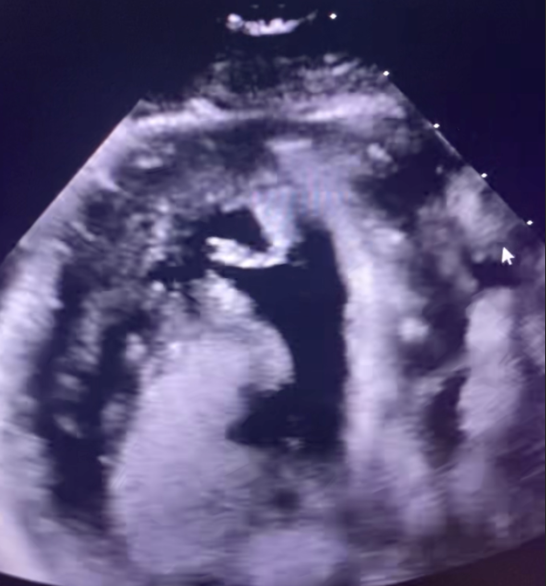

- Bedside Echocardiogram: Left ventricular apical hypokinesis with preserved ejection fraction (60–65%) and borderline concentric LV hypertrophy; no valvular abnormalities or pericardial effusion

The patient tolerated the procedure well. A repeat echocardiogram the following day revealed a left ventricular apical thrombus. He was initiated on triple antithrombotic therapy with aspirin, clopidogrel, and apixaban. His hospital course was uncomplicated. He remained hemodynamically stable with no recurrence of symptoms and was discharged on hospital day 4.